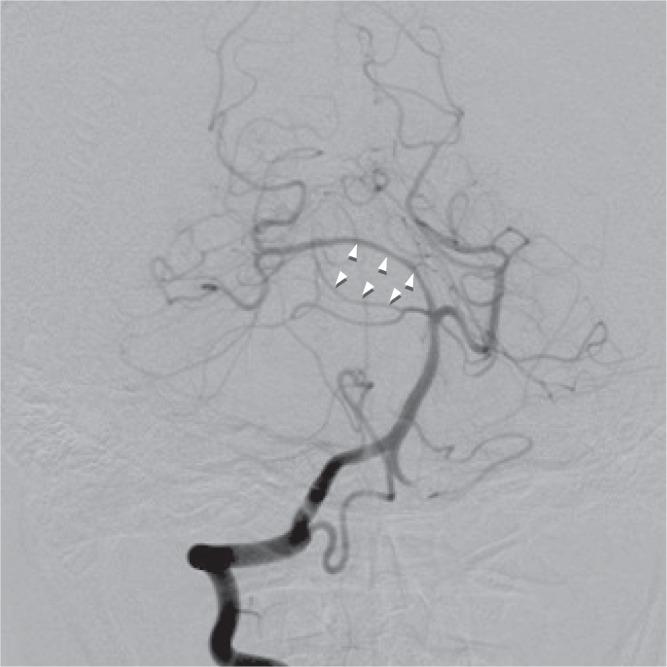

A 37-year-old woman presented with an extremely rare large oculomotor schwannoma associated with acute hydrocephalus manifesting as semicoma and anisocoria. Brain computed tomography and magnetic resonance imaging revealed a tumor in the oculomotor cistern. Cerebral angiography revealed separation of the posterior cerebral artery (PCA) and superior cerebellar artery (SCA). The tumor was removed subtotally by two stage surgery. Histological examination revealed ordinary schwannoma. The diagnosis of oculomotor nerve schwannoma was based on the intraoperative finding of the tumor origin in the oculomotor nerve. Oculomotor nerve schwannoma can cause acute hydrocephalus and manifest as impaired consciousness. The angiographical separation of the PCA and SCA was very useful for the preoperative diagnosis of oculomotor nerve schwannoma.

一名37岁女性因极其罕见的大型动眼神经鞘瘤伴急性脑积水就诊,表现为半昏迷和瞳孔不等大。脑部计算机断层扫描和磁共振成像显示动眼神经池内有肿瘤。脑血管造影显示大脑后动脉(PCA)和小脑上动脉(SCA)分离。通过两阶段手术次全切除了肿瘤。组织学检查显示为普通型神经鞘瘤。动眼神经鞘瘤的诊断基于术中发现肿瘤起源于动眼神经。动眼神经鞘瘤可导致急性脑积水并表现为意识障碍。PCA和SCA的血管造影分离对动眼神经鞘瘤的术前诊断非常有用。